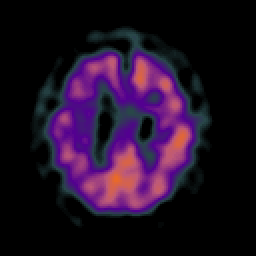

Motor Neuron Disease: overlay -- Slice #18

[Home][Help][Clinical] Slice 18